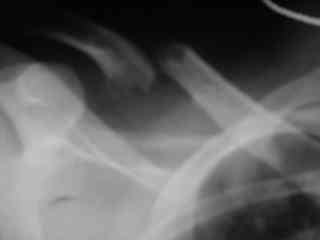

Bolnogo operirovali plastinami, snimky zdes'.

CIMG1145.JPG

Похоже, все прошло по плану. Поздравляю с успешной операцией!

Pneumatorax hirurg punctiroval i lechil dalshe, operasia zanimala 1 chas 35 minut, ni bilo problem ossobih.